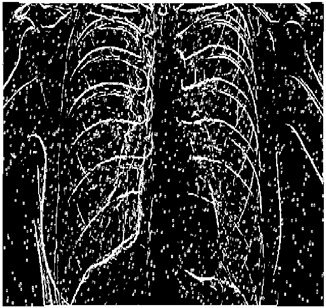

Table 5. X-ray Images.

X-ray 1X-ray 2X-ray 3X-ray 4X-ray 5

Mathematics 10 02421 i004 Mathematics 10 02421 i005 Mathematics 10 02421 i006 Mathematics 10 02421 i007 Mathematics 10 02421 i008

For the purpose of simulation, we consider two sets of images: (1) three images from MATLAB repository (Table 4) and (2) five X-ray images available online (Table 5).

Table 8 shows that:

• In all cases, the Canny edge detector detects more edge pixels than both fuzzy compositions.

• As the level of noise increases, Canny and standard composition become adversely affected by the noise, and still more edges are detected by Canny; however, most of the detected edges by Canny are misdetections due to the impact of noise. As is obvious from this table, the smooth composition provides a better image with reduced noise density.

• In all cases, the PFOM value for the smooth composition is always greater than the PFOM value for the standard composition, according to Table 6.